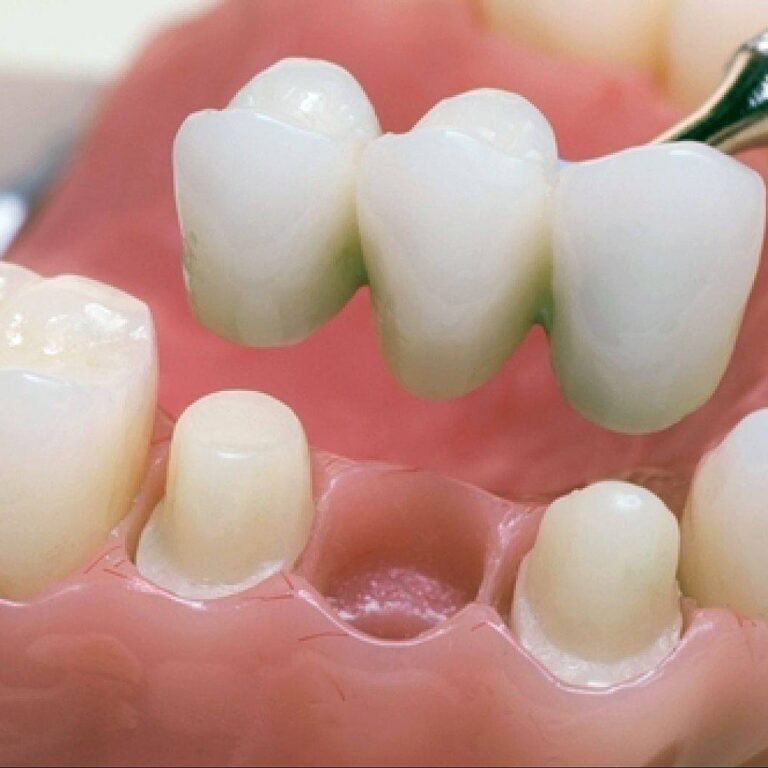

In modern dentistry, temporary constructions play a far more important role than may appear at first glance, because they are not merely an intermediate stage between preparation and final restoration,